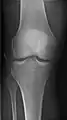

- زانو - AP و جانبی. پروجکشنهای داخلی کندیلار(Condular) در صورت درخواست.

زانوی راست، قدامی خلفی

زانوی راست، جانبی

استخوان کشکک (کمی انحراف) افق مرئی